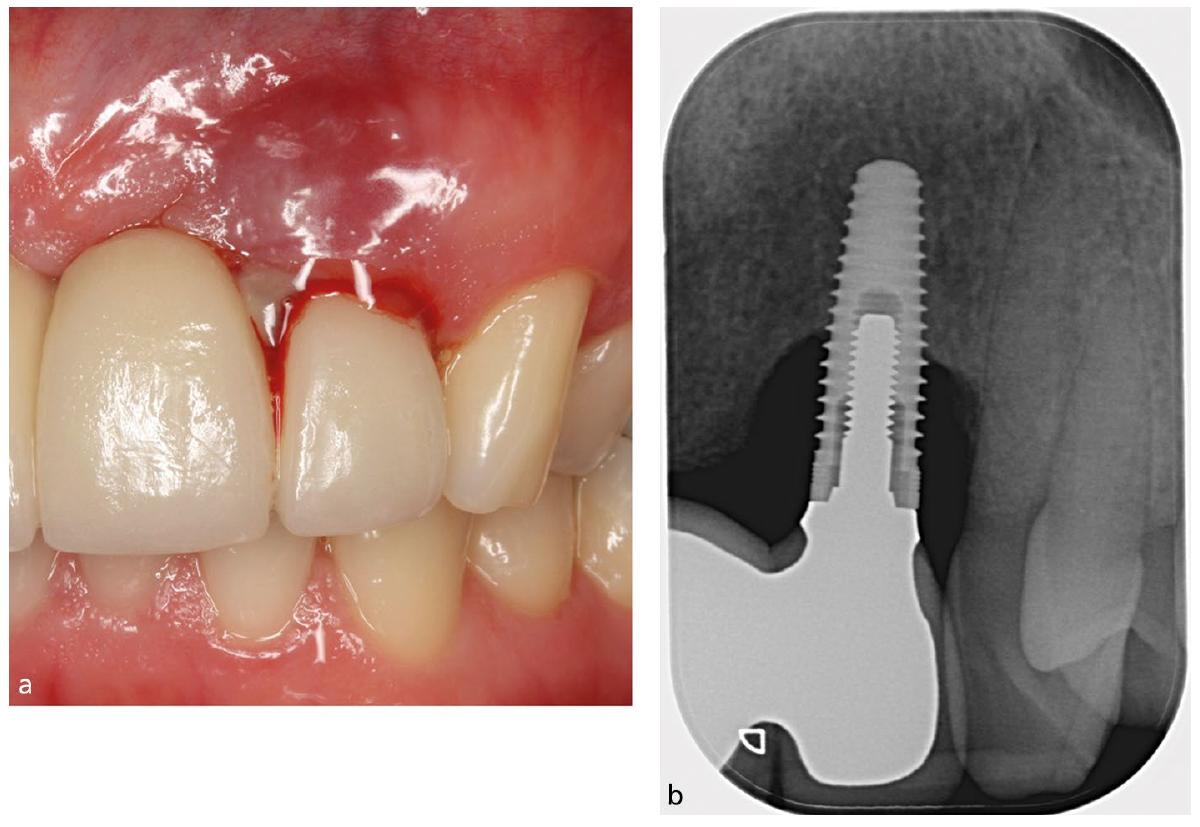

Clinical and radiologic signs of periimplant mucositis

Clinical and radiologic signs of periimplantitis

- Peri-implant mucositis affects the peri-implant mucosa (soft tissues) and is characterised by clinical signs of inflammation (BoP) without loss of supporting bone

- Peri-implantitis is characterised by clinical signs of inflammation (BoP) in addition to progressive bone loss

- When clinical signs of inflammation are detected (BoP, deepening probing depths), an intra-oral radiograph confirms a

diagnosis depending on whether there has been progressive or continuing peri-implant bone loss (peri-implantitis) or not (periimplant mucositis).